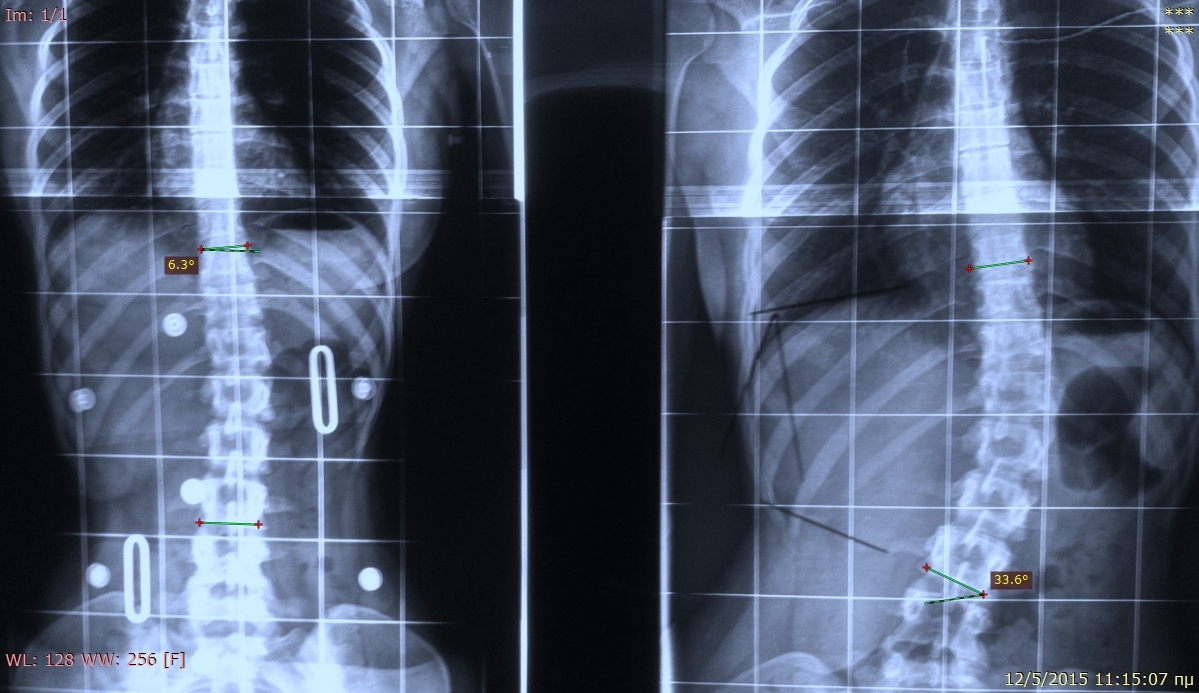

Фото: commons.wikimedia.org, Scoliosis Treatment Crass Cheneau, Creative Commons Attribution-Share Alike 4.0 International license.